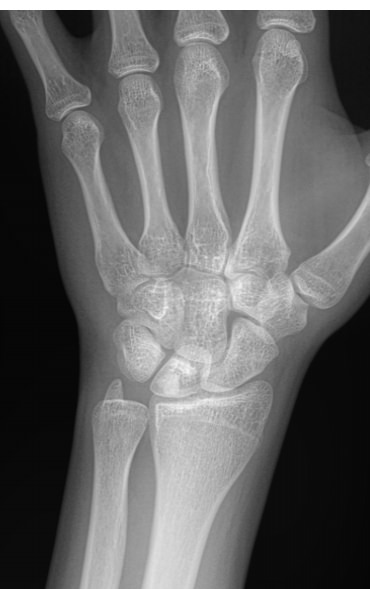

Для диагностики патологии суставов обычно достаточно рентгеновского снимка ― на нем отлично будут видны все особенности болезни, а также ее стадия. Чтобы выбрать правильную тактику лечения, необходимо определить, на каком этапе развития заболевания пациент обратился за помощью.

Что показывает рентген пястно-запястных суставов

На снимке могут быть видны следующие патологии:

• Сужение или расширение суставной щели, обызвествления, выросты или выпот в ней;

• Несовпадение элементов сустава друг другу из-за вывиха;

• Изменения в костной ткани и надкостнице ― в результате ее разрежения, уплотнения или воспаления;

• Утолщение мягких тканей;

• Реже встречаются переломы и опухоли.